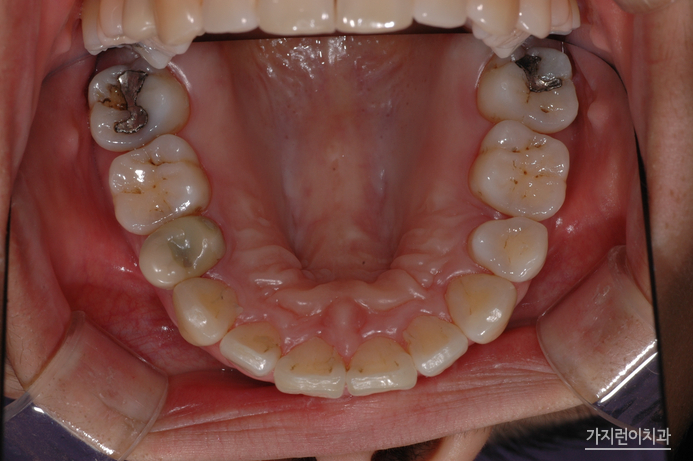

해당 환자의 경우 치아 문제에만 국한되어있는 게 아니라 골격적인 문제가 동반된 케이스였습니다. 때문에 안정적인 결과를 얻기 위해서 수술교정을 진행하게 되었는데요. 돌출입 양상을 보면 치아가 문제가 아닌 골격적인 문제인것을 확인해볼 수 있었습니다. 이런 케이스를 무리하게 비수술로 진행하게 되면 앞니가 들어간 옥니가 될 수 있겠는데요. 환자의 구강골격을 확인한 후에 수술교정으로 플랜을 수립해 진행한 결과 안정적인 결과를 얻을 수 있었습니다.

바로 이 모습입니다. 수술교정의 경우 안모변화가 큰 편인데요. 돌출되었던 입이 들어가고 턱 라인까지 정리된 모습을 얻을 수 있기 때문에 둔탁한 모습에서 날렵한 모습으로 눈에 띄게 변화한 것을 확인해볼 수 있었습니다. 여기에 가지런한 치열은 긍정적인 이미지를 불러일으키는데요. 환자의 상태에 따라서 적합한 교정방식을 선택할 수 있는 곳. 교정전문치과 서울가지런이치과 교정과 의원에서 도움 받아보는 건 어떨까요?